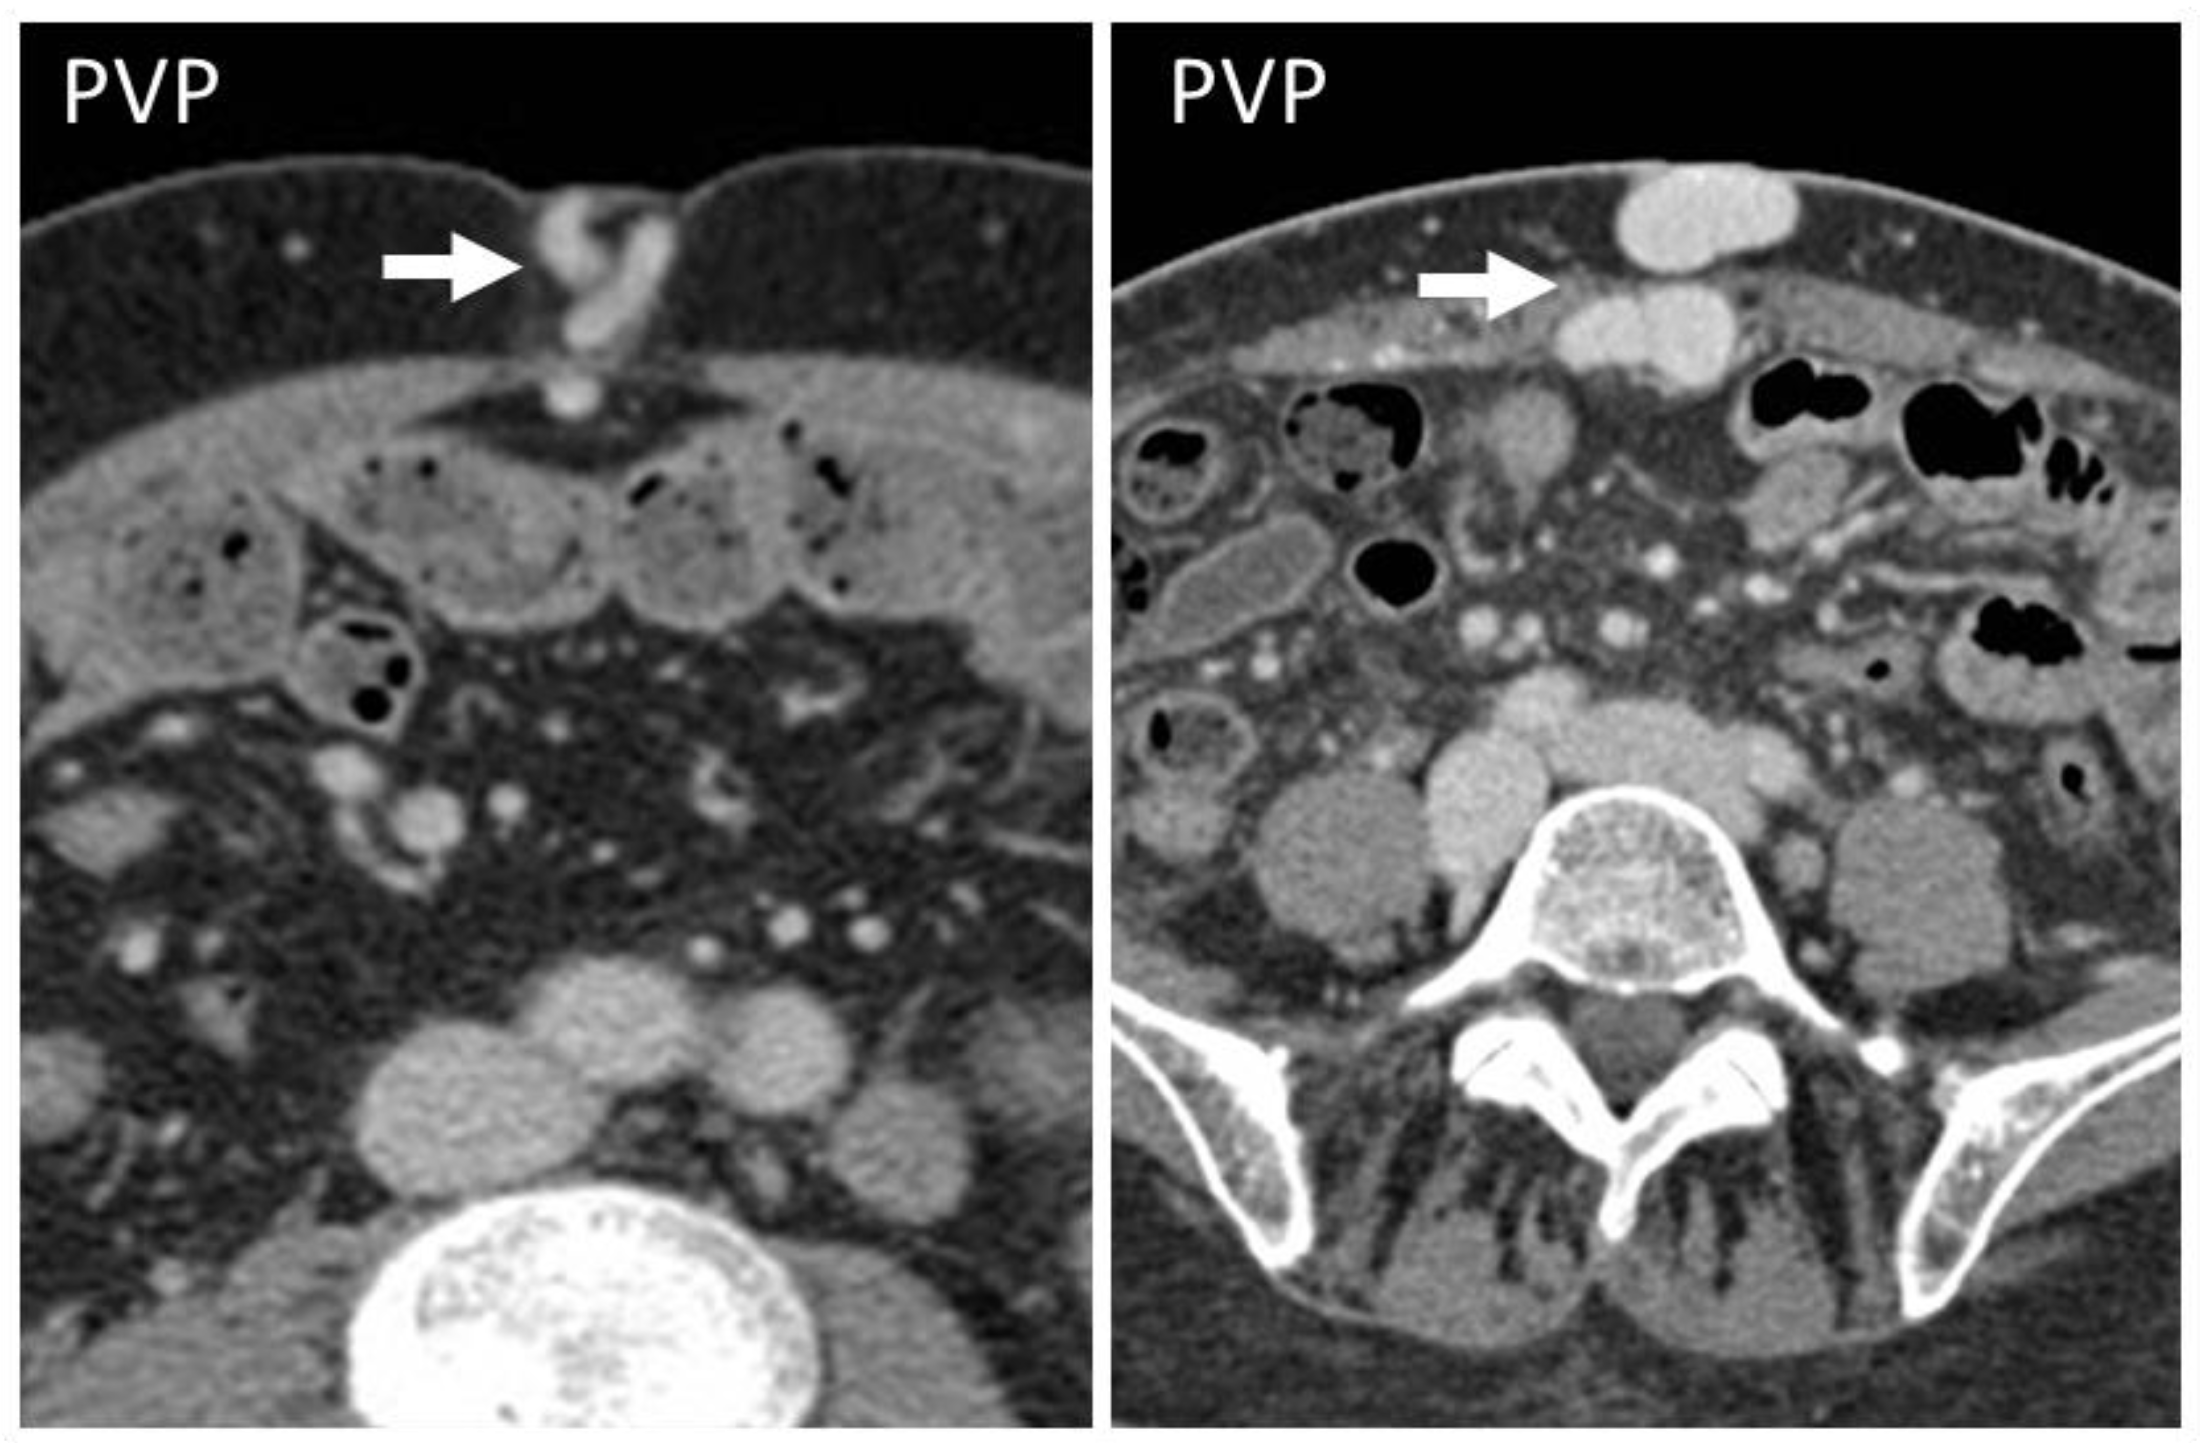

Figure 8. CT appearance of “caput medusae” on axial, contrast-enhanced CT scan on portal venous phase in two cirrhotic patients, as a result of the recanalization of the umbilical vein due to portal hypertension. This appearance is due to tortuous vessels (arrows) reaching the abdominal wall at the level of the navel.

Acquired shunts in the abdominal wall might be a sign of portal hypertension or inferior vena cava obstruction, which are both conditions to assess and not underestimate. Indeed, if untreated, the first one may lead to cirrhosis and hepatocellular carcinoma, and the latter can lead to pulmonary embolisms. Acquired shunts are caused by dilatation of the paraumbilical veins within the round ligament [26,27,28].

The paraumbilical veins will connect the superior and inferior epigastric veins in the rectus sheath with the left branch of the portal vein at the umbilicus [29], with an appearance called “caput medusae”.

CT should be preferred, in order to study all of the other signs of portal hypertension [27]. Treatment of shunts is linked to the treatment of the underlying causative condition, although in some cases bleeding can also be seen (Figure 8).